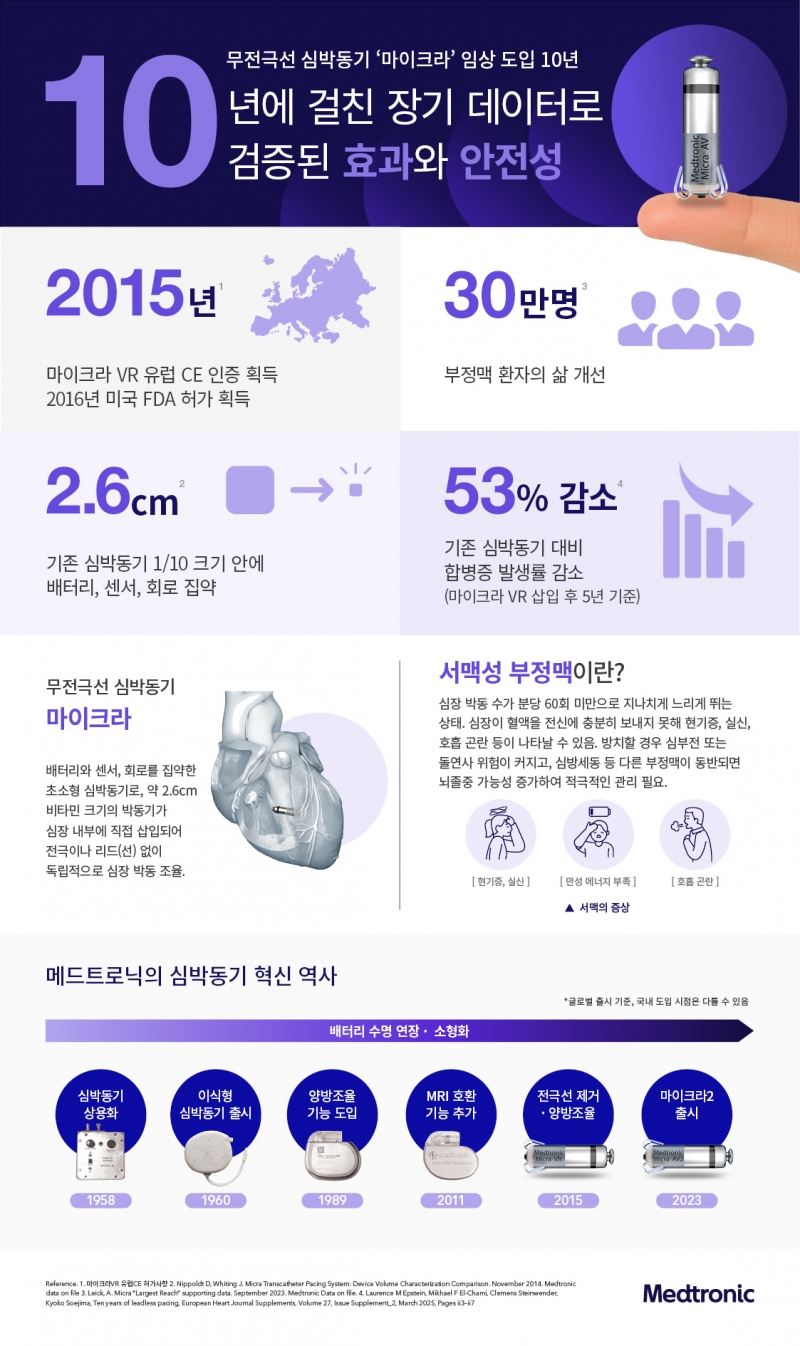

메드트로닉 한국 법인 메드트로닉코리아(대표 유승록)가 무전극선 심박동기 ‘마이크라(Micra)’ 출시 10주년을 맞아 임상적 성과를 조명하는 인포그래픽을 공개했다.

메드트로닉은 지난 2015년 기존 심박동기 대비 10분의 1 수준인 2.6cm 크기 마이크라를 선보이며 무전극선 심박동기 시대를 열었다.

2015년 유럽에서 CE 마크를 획득한 이래 한국을 포함한 미국, 유럽, 일본 등 전 세계적으로 10년간 30만 명 이상 부정맥 환자들의 삶을 개선하는데 기여했다.

유럽심장학회지(European Heart Journal)는 2025년 특집호 ‘무전극선 심박동기 10년의 여정(10 Years of Leadless Pacing)’을 발간하며 지난 10년을 “심박동기 기술 혁신의 시대(Revolution in pacemaker technology)”로 규정했다.

무전극선 심박동기 진화 과정과 적용 분야, 시술 후 관리, 젊은 환자로 적용 확대 트렌드 등을 다루는 7개의 논문으로 구성된 특집호에서는 마이크라 임상이 가장 활발하게 언급됐다.

그 중에서도 장기 추적 데이터로 마이크라 안전성과 효과를 입증한 연구가 주를 이뤄 분야를 선도하는 지위를 확인시켰다.

특히 전 세계 179개 센터에서 1817명의 환자를 시술 후 5년 간 추적 관찰한 시판 후 연구(Post-approval registry)에 따르면 마이크라 VR은 5년 시점 주요 합병증 발생률이 4.5%였으며 감염으로 인해 기기 제거가 필요한 경우는 없었다.

마이크라 AV로 치료받은 모든 미국 메디케어 가입자(7471명)를 추적한 결과에서도 2년 시점에 5.3% 중증 합병증 발생률을 보이며 기존 심박동기 대비 일관되게 낮은 합병증 발생률을 입증했다.

한편, 메드트로닉은 1958년 배터리 외장형 심박동기를 상용화하며 심장 박동 치료 시대를 열었으며, 이후 이식형 심박동기, 양방조율 심박동기, MRI 환경에서도 사용할 수 있는 심박동기를 선보이며 환자 치료 선택지를 넓혀왔다.